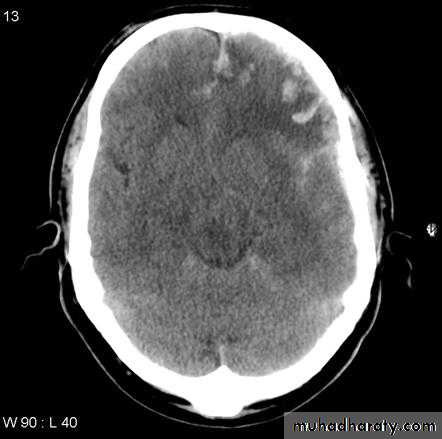

Common CT findings of traumatic brain injury